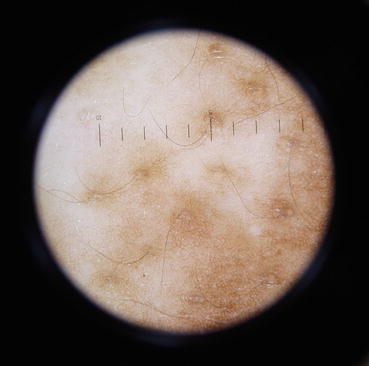

Fig. 22.4

Perifollicular pigmentation with reduced pigment network in an early lesion of vitiligo

Thatte and Khopkar [3] in their recent study have reported the following dermoscopic findings in evolving vitiligo: reduced/absent (Fig. 22.2), reversed pigmentary network (Fig. 22.3), perifollicular and perilesional hyperpigmentation (Fig. 22.4), and a diffuse white glow under UV light. The predominant findings noted were reduced (40 %), absent (30 %), and reversed pigmentary network (20 %).

22.5 Dermoscopic Features to Assess the Stage of Vitiligo

Assessing the stability of vitiligo when considering vitiligo surgery is another area where the dermoscope comes as a handy tool. There are various well-described clinical signs of progressive activity like confetti macules, koebnerization, onset of new macules, and trichrome. In a Chinese study [9], it was reported that residual perifollicular pigmentation was observed in 91.94 % of patients with progressive vitiligo when compared to 62.86 % of those with stable vitiligo. There was no residual perifollicular pigmentation observed in nonvitiligo depigmented lesions. The presence of telangiectasia, early reservoirs of pigmentation, and perilesional hyperpigmentation was reported to be related to the stage of vitiligo and treatment history of patients.